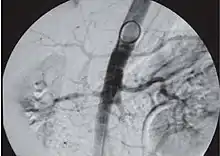

- Ренгеноконтрасна ангіографія — «золотий стандарт» в діагностиці стенозу ниркових артерій. Ангіографічне обстеження можна проводити, обминаючи скрінінгові процедури (радіоізотопні, ультразвукові), якщо імовірність звуження ниркової артерії висока (слід брати до уваги ризик, що виникає внаслідок інвазивних методів — нефротоксична дія контрастної речовини, можливість емболізації холестериновими масами чи ураження стінки судини);

- Як альтернативу до агіографічного методу застосовують внутрішньо артеріальну дигітальну субтракцйну ангіографію (ДСА);